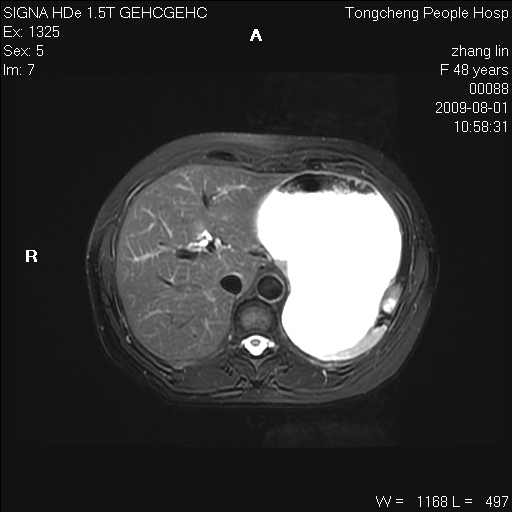

女,48岁。健康体检,彩超发现右肾占位性病变。平素健康。

临床诊断:右肾占位性病变,性质待定(囊肿?肿瘤?)。

上中腹部mr平扫+增强扫描,图像如下:

右肾上极见一类圆形病灶,t1wi呈等信号t2wi呈等高混杂信号,三期增强无强化,边界清---考虑囊肿出血。

同反相位均表现为等信号,病变无强化,考虑含蛋白的囊肿可能,弥散加权相或许有些帮助,